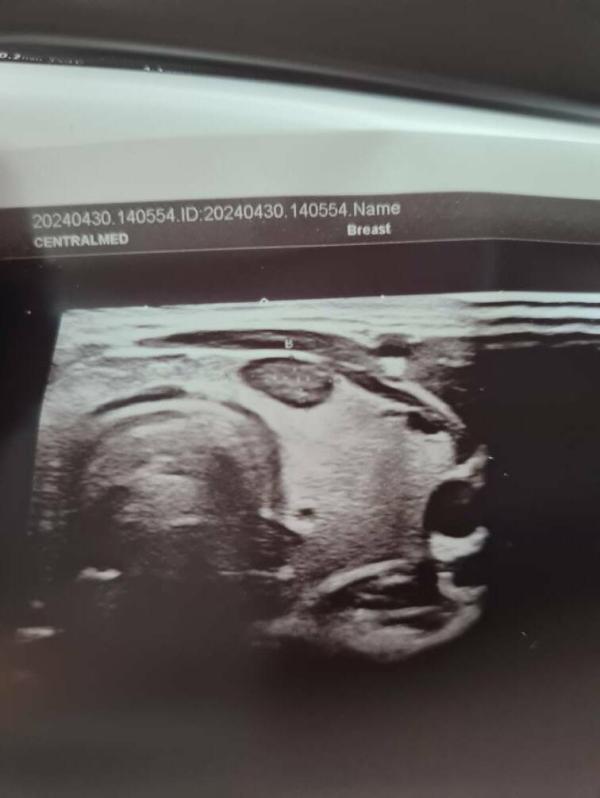

На втором фото абсолютно случайная находка. Молодая девушка, жалоб никаких нет, а вот такой не самый хороший узел нашёлся.

К слову, у взрослых узлы и другие проблемы щитовидной железы встречаются очень часто, особенно у женского пола. У детей редко, но в % соотношении гораздо больше злокачественных. Узлы не болят, не беспокоят, гормоны в большинстве случаев в норме. Как же их находят? Либо случайная находка при диспансеризации/осмотре эндокринолога, либо когда уже он огромный, либо уже когда все запущено и появляются жалобы.